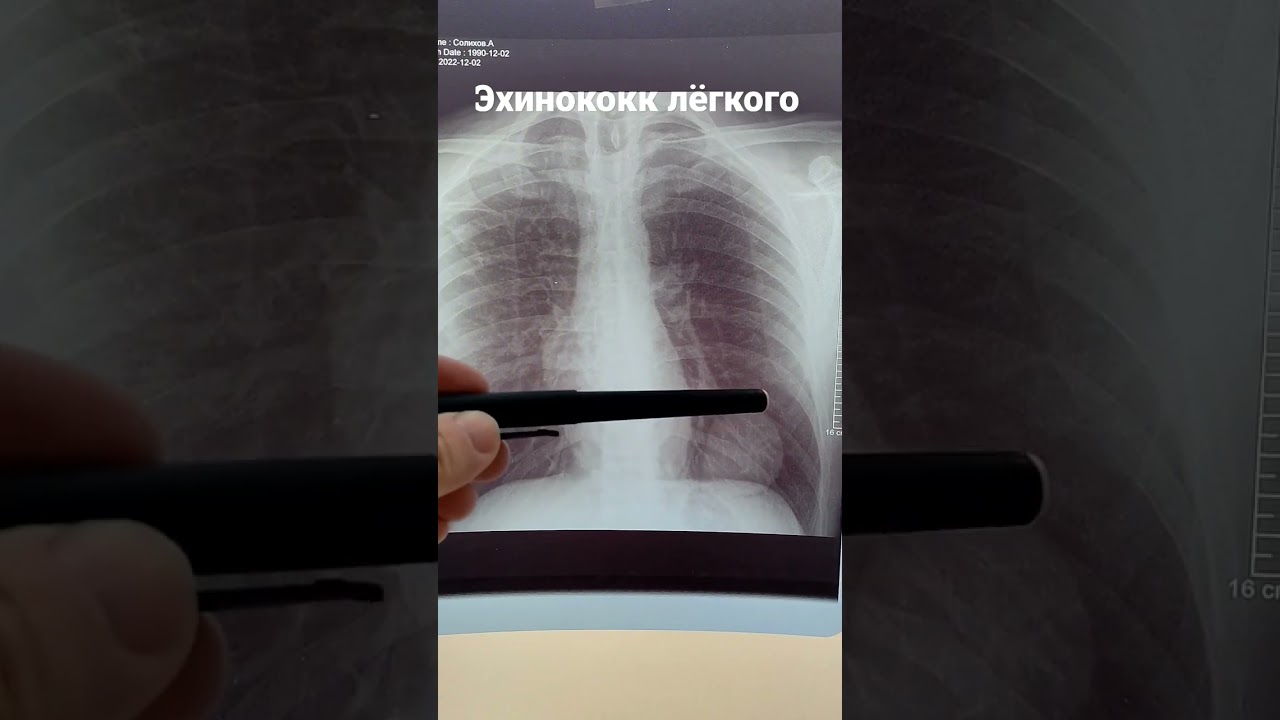

| Диагностика | Рентгенография, КТ, МРТ (выявление деструкции кости, кист), серологические тесты (ИФА на антитела к эхинококку), биопсия (гистологическое подтверждение). | Комплексный подход необходим для подтверждения диагноза и оценки распространенности процесса. |